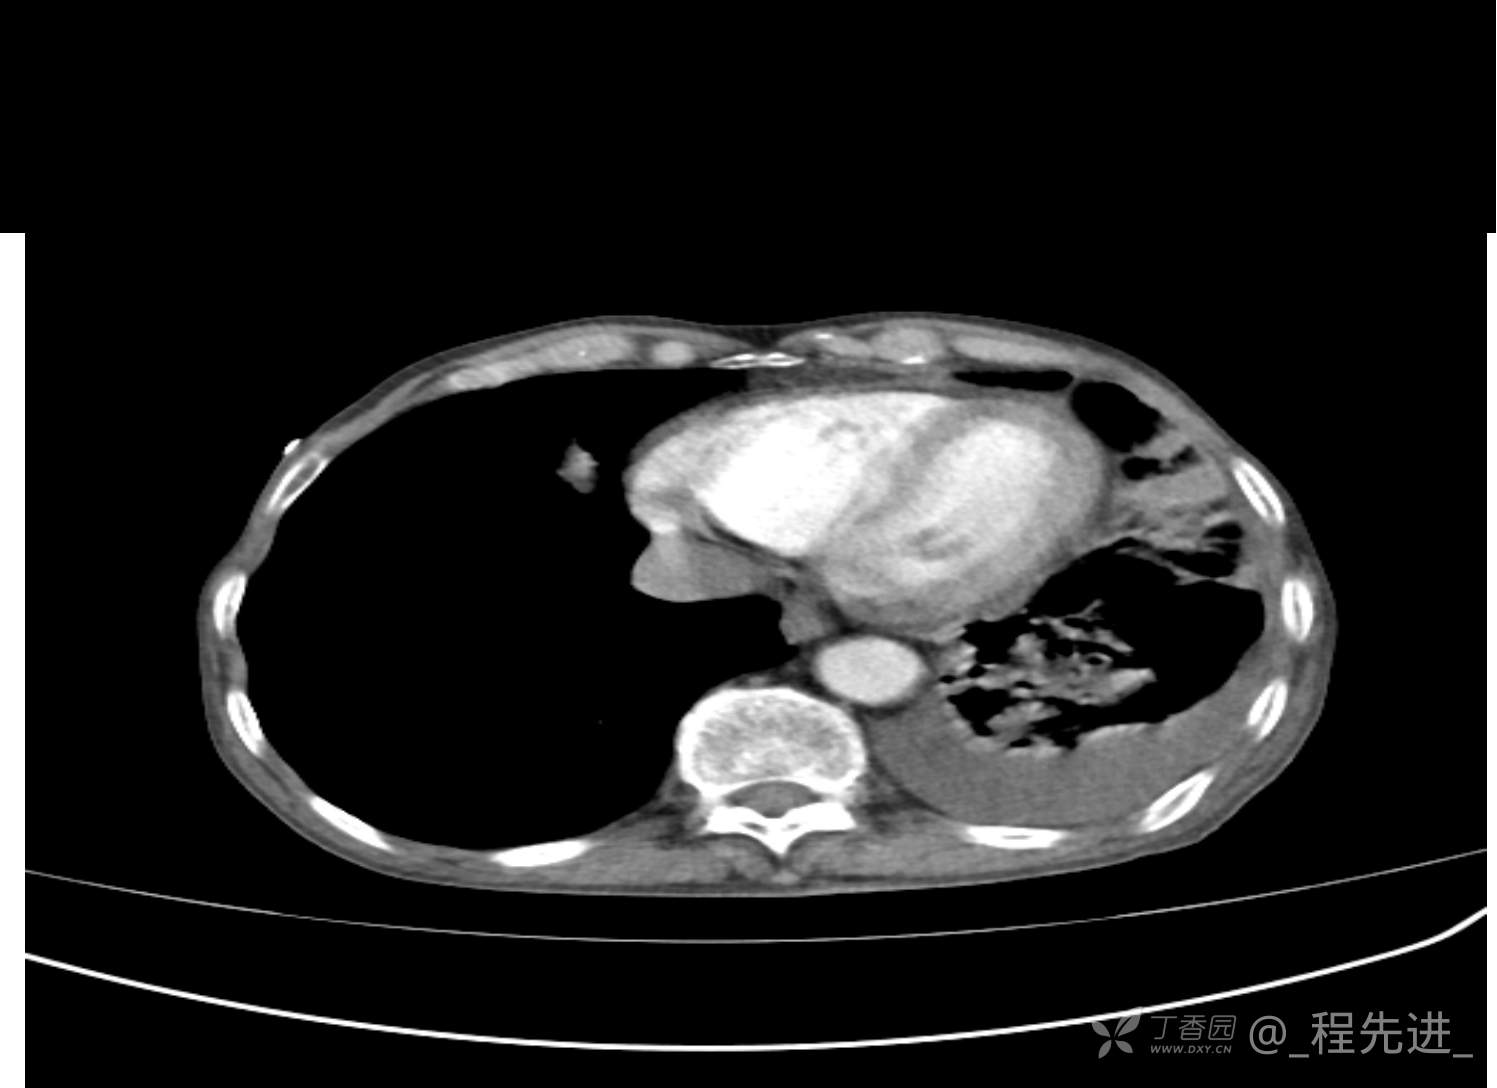

患者性别:男

患者年龄:81岁

简要病史:反复咳嗽、咳痰20余年,加重1周。两肺呼吸音低,可闻及散在干湿啰音。